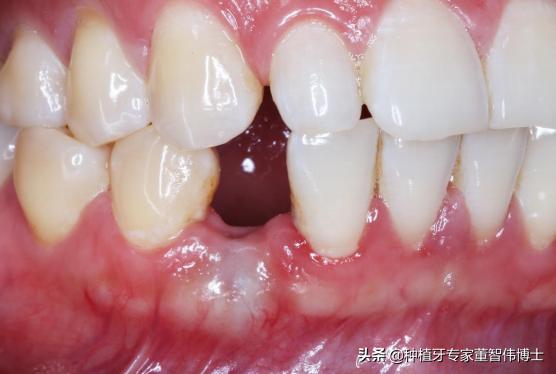

口内照-术后6月